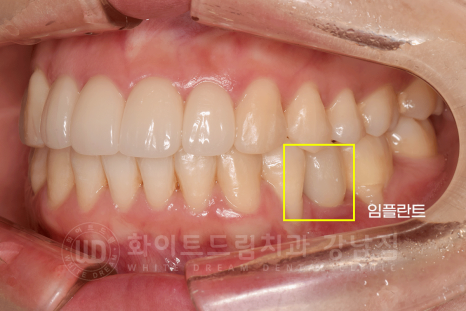

교정 후 입매 라인 변화입니다.

동일 인물이며 동일 환경에서 촬영되었습니다.

콤플렉스였던 사나워 보이는 치열과 부자연스럽던 입매 라인도 모두 개선되었고

무엇보다 임플란트 치료까지 동반했는데 치료가 빨리 끝나셔 환자분이 굉장히 좋아하셨답니다. ^^

치아교정 후 블랙 트라이앵글 & 뻗은 치아 모양의 개선을 원하셔서

상악 앞니 전치부 4개는 라미네이트 치료를 받으셨습니다.